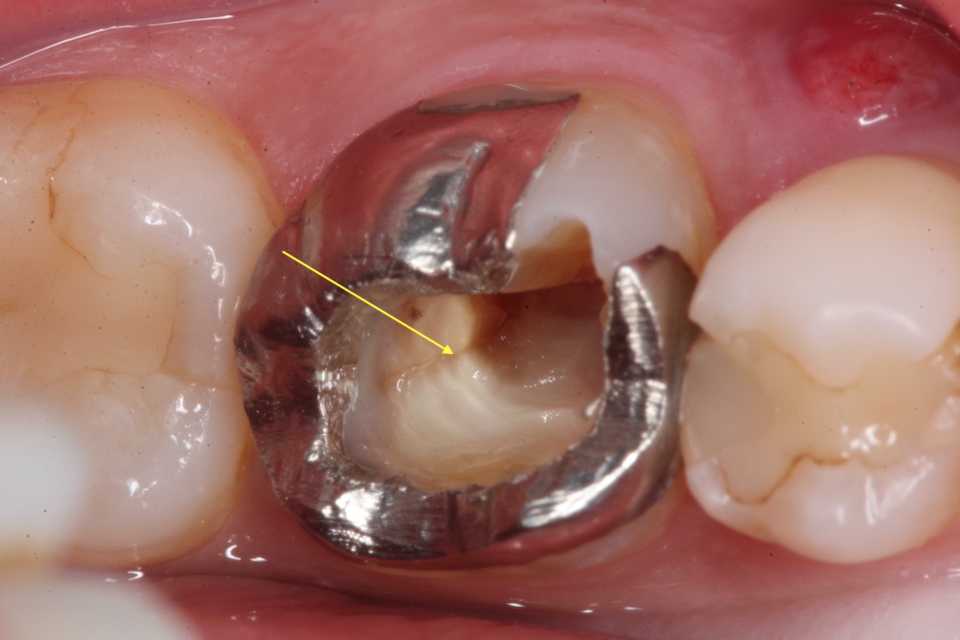

50代女性、左上7、外傷性近心辺縁隆線破折、クラック、自覚症状なし前回のつづきhttps://plaza.rakuten.co.jp/mabo400dc/diary/202509240000/鋳造で作るという作業は現在の歯学部で教えているのかどうか分からないが、最近のトレンドとして口腔内スキャナー、CAD/CAM、3Dプリンターで作るという流れになっているようだが、まだまだ機械が高いし、CRすらマトリックスを3DプリンターでCRを注入するとか、面倒なことをやっているらしい。その場ですれば数分で終わるのに、アホとしか言いようがない。僕が歯学部にいた頃でさえ鋳造実習はおざなりなもので、歯の作成は技工士に丸投げするので、真面目にやらなくてもよいという気満々だった。そういうネガティブ思考を乗り越えたところにワンオペ歯科治療はあるのだが。。今日は口腔内セットまでで一応終わり。銀合金は貴金属(パラジウム合金含む)と違いスーパーボンドの接着性が良い。

50代女性、左上7、外傷性近心辺縁隆線破折、クラック、自覚症状なし前回のつづきhttps://plaza.rakuten.co.jp/mabo400dc/diary/202509170000/外傷性に破折しそうな歯を補強冠で割れにくいようにするというのは対症療法としては有効だ。技工作業も難しくないので、ワンオペでできると思う。外注しようにもCAD/CAM、3Dプリンター等では作れないし、技工士も作ったことはないと思うので、断られる可能性が高い。銀合金で良いのでコストも低く抑えられる。では技工室の作業からバイトも対合歯も不要で技工作業も超基本のロストワックス法で簡単なので自分ですると良い。つづく